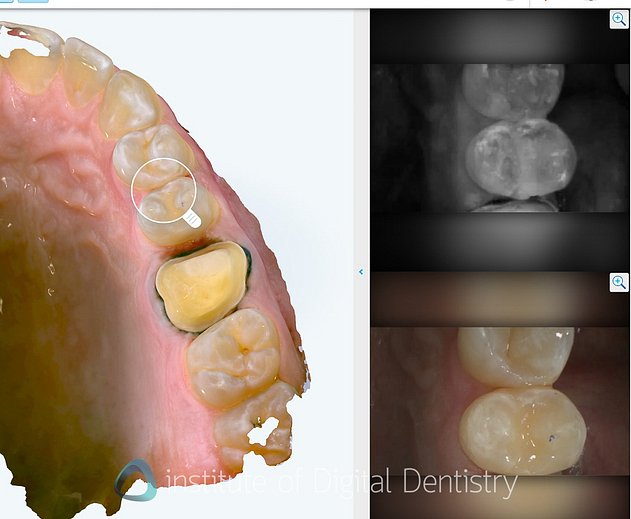

NIRI Technology: Near-infrared imaging aids in detecting interproximal caries without harmful radiation. According to Align, the technology demonstrates 66% greater sensitivity than bitewing radiographs based on clinical studies. No doubt, this is the best interproximal caries detection currently available in any scanner.

Personally, I believe the education surrounding near-infrared images in scanners is lacking, and most dentists are likely unfamiliar with what they are looking at or what is diagnostic. That is just my 2 cents. Overall, I have to say it's great tech and provides a nice diagnostic tool and perhaps a useful alternative if the patient refuses bitewing X-rays.

Integrated Intraoral Camera: High-definition intraoral images are captured while scanning, and multi-angle views of each tooth can be seen. Clinical applications include displaying and tracking gingival health with realistic images.

The UI is very well done here; rather than showing you multiple images, it presents you with a magnifying glass that you can put on any tooth. Then the software shows you the NIRI images and intraoral images captured in that site.